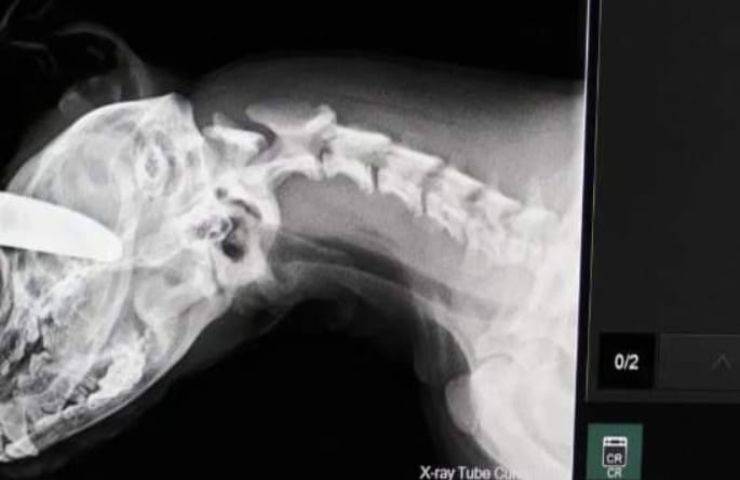

Le autorità avvertite per tempo dal testimone oculare si sono precipitate sul luogo agendo con tempestività e compassione, gli agenti vedendo la situazione in fatti hanno immediatamente trasportano il cane ferito al Williamsburg Small Animal Hospital, dove i medici hanno portato immediatamente il cucciolo ferito in sala operatoria rimuovendo il coltello e somministrando antibiotici e le cure necessarie al il processo di guarigione.

Mentre l’uomo si trova in carcere e si sta stabilendo la data del processo per crudeltà nei confronti degli animali, il veterinario locale ha riferito che il cucciolo nonostante la grave ferita sarebbe in via della guarigione.